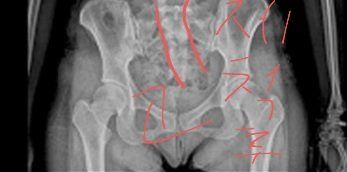

(엑스레이사진은 제것이 아니에요)

병원가서 엑스레이 찍고 일자허리에 4번척추에 디스크 약간 있다고 했어요. 또 결과 사진에 이런거 비슷한거 있었어요

(위에 사진)

방향은 맞는지 모르겟어요

도수치료랑 진통제처방 해주셨어요 엑스레이 찍었을 때 척추가 특이한게 이랬어요